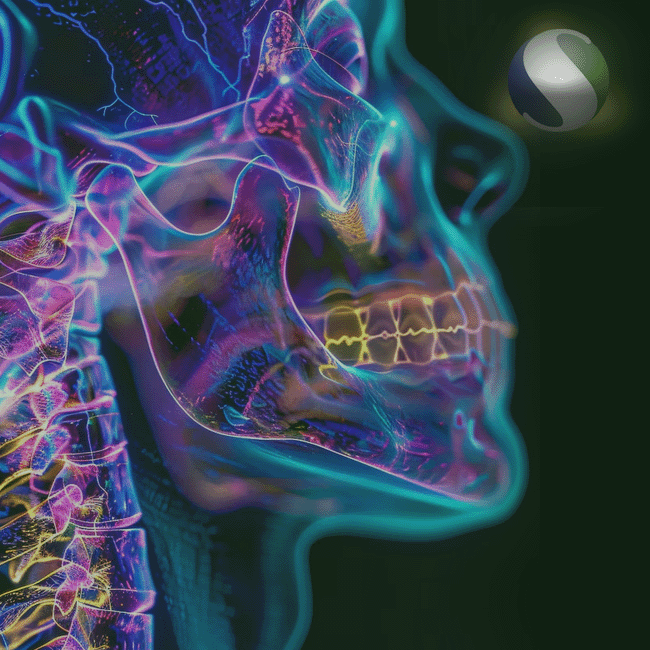

NEUROCIRURGIA

A Orthoset atua com excelência na área de neurocirurgia, oferecendo soluções que atendem às exigências de um dos campos mais sensíveis e desafiadores da medicina. Nossa linha contempla produtos desenvolvidos com alta tecnologia e precisão, fundamentais para procedimentos que envolvem a integridade do sistema nervoso central. Trabalhamos com marcas reconhecidas e priorizamos a segurança, a eficiência e a confiabilidade em cada item disponibilizado.

BUCOMAXILO

A Orthoset oferece uma linha dedicada à cirurgia bucomaxilofacial, voltada para o tratamento de traumas, deformidades e patologias da face. Nossos produtos são desenvolvidos com materiais de alta performance, que aliam resistência, precisão anatômica e fácil adaptação aos procedimentos cirúrgicos. Essa linha é resultado de um compromisso com a funcionalidade estética e funcional, contribuindo significativamente para a recuperação e autoestima dos pacientes.